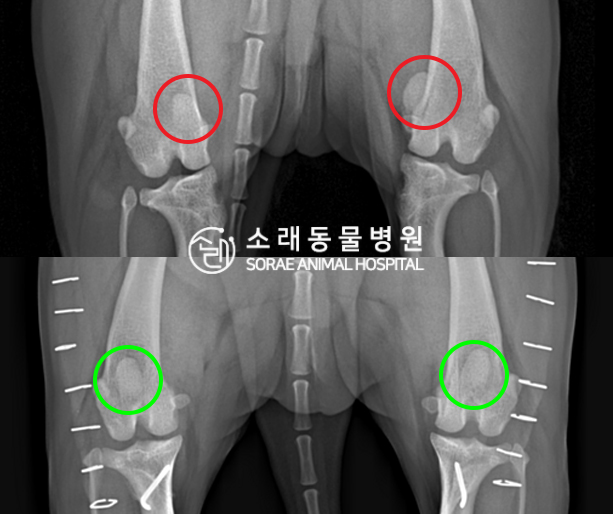

수술전과 수술후에 촬영한 뽀송이의 슬개골

방사선 사진입니다. 나란히 놓고 비교해보니

슬개골의 위치에 확연한 차이가 있는 것을

확인해 볼 수 있는데요. 내측으로 탈구되어 있던

슬개골이 원래 제자리인 활차구에 예쁘게

자리 잡고 있는 모습을 확인할 수 있었습니다.